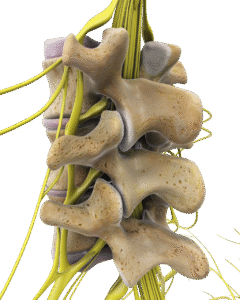

Back pain

Il dolore lombare è una condizione molto frequente. Può avere diverse cause, come problemi muscolari, articolari o discali, e spesso limita le attività quotidiane.